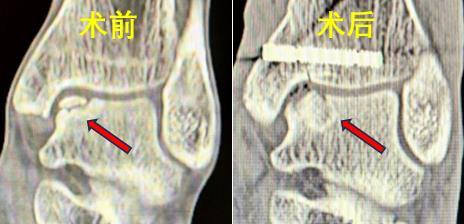

38岁的男性患者蒋某与43岁女性患者潘某,均因踝关节扭伤导致距骨软骨损伤,接受保守治疗后效果不佳,疼痛反复,严重影响日常生活。中南大学湘雅三医院骨科足踝外科团队接诊后,通过详细问诊、体查及影像学检查,明确诊断为“距骨骨软骨损伤(HeppleIII型及V型)”。

骨科副主任医师张克祥介绍,在日常生活中,“崴脚”,即踝关节扭伤,是导致距骨软骨损伤的常见原因,但由于软骨自我修复能力较差,所以软骨损伤是公认的治疗难题。针对患者病情,金年会(JinNianHui)体育官网团队经过讨论,决定采用自体骨膜-骨栓移植技术修复损伤区,同时为其定制3D打印导板,以实现精准截骨,缩短手术时间、减少副损伤。

手术当日,在麻醉科团队的密切配合下,张克祥带领手术团队先通过关节镜彻底清理踝关节内增生滑膜及疤痕组织,再使用3D打印导板于内踝截骨,北京pk10显露软骨损伤区并彻底清理病灶组织;随后,从患者自身髂骨提取带骨膜的骨栓,将其植入距骨软骨损伤处,整个手术过程顺利,患者术中生命体征平稳。术后,在护理团队的精细化理疗与康复指导下,患者踝关节疼痛症状显著缓解,目前已逐步进行功能锻炼,患者对治疗效果非常满意。